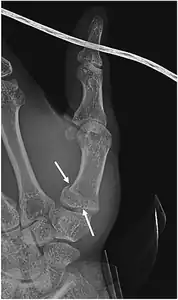

| Bennett fracture on x-ray | |